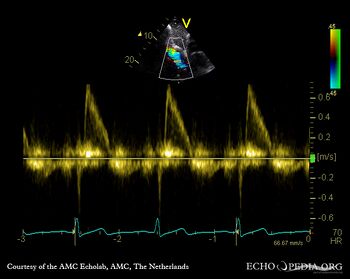

PLAX: vegetations on aortic valve, dilated left ventricle and left atrium PLAX: Color Doppler, severe aortic regurgitation, excentric jet, and moderate mitral regurgitation